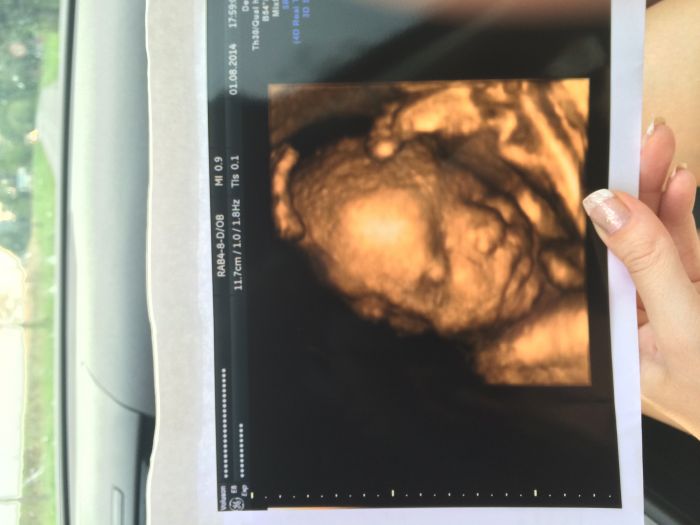

Zdravim vsechny:-) Tak v patek na 4D to vypadalo,ze se nam prcek neukaze. Ma hlavicku tam,co ja zaludek a ma tam taky obe ruce a obe nohy. To vse pred oblicejem. A aby toho nebylo malo,jeste ma nad hlavou na predni strane placentu. Ale zhruba po pul hodine,kdy jsem se tocila jak spekacek nad ohnem ze strany na stranu a mezi tim na zada,ktera se mi kousla hned,jak jsem lehla na to temer rovne lehatko,se zadarilo udelat par snimku:-) Takze vzorek poslu :-)